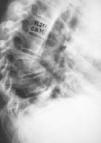

El uso del TAC y la RM ha supuesto un avance fundamental en el estudio de mal de Pott, ya que permiten un conocimiento exacto de la extensión de las lesiones y además conocer la repercusión del proceso en el canal medular. Aunque la TAC aporta un magnífico estudio de las lesiones óseas (Fig. 7), las ventajas de la RM es que, además de una mayor precisión, aporta una mejor imagen topográfica y permite conocer las posibles alteraciones meníngeas o medulares, así como las repercusiones del proceso en el canal medular22 (Fig. 8). Actualmente la incorporación de la TAC de tipo helicoidal ha mejorado los estudios clásicos anteriores.

Figura 7. Lesiones destructivas del cuerpo vertebral torácico con imagen de absceso prevertebral.

Figura 8. Imagen de RM con absceso intrarraquídeo.

Nuestra experiencia, coincidente con la de otros autores,4,20,22 indica que hay un menor número de cuerpos afectos en la osteomielitis vertebral. En T1 la intensidad es más homogénea en la osteomielitis que en las lesiones tuberculosas, y con respecto al estudio de los abscesos tras la administración de gadolinio en los de origen tuberculoso el reforzamiento de los bordes es mucho mayor que los de etiología inespecífica.